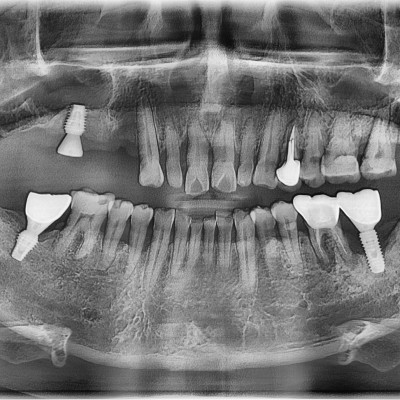

임플란트 재수술 #12.13.22 타원 임플란트 제거 후 임플란트 수술+치조골 이식술 시행하였습니다.

임플란트 재수술 #14.15.16.17 타원 임플란트 제거 후 임플란트 식립+ 치조골 이식술 시행하였습니다.

작성자 이턱이 작성일 01-27 조회 111